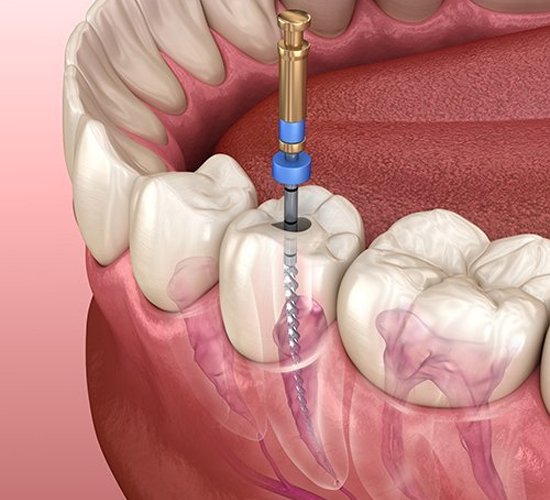

Root Canal Treatment

dvanced root canal treatment in Fujairah to relieve pain and protect your natural tooth.